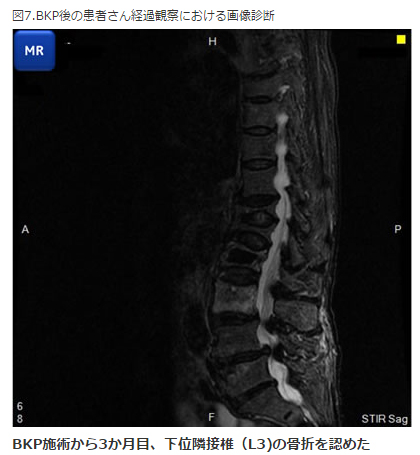

(5)BKP後の測定

椎体に骨セメントを注入してあるため手術部位以外、所謂、腰椎での測定は避けて、大腿骨での骨密度測定を行います。更に隣接椎体の経過も一般撮影 MRi DXA装置PRODIGYなどで注意して観察しています。図7「BKP後の患者さん経過観察における画像診断」をご覧ください。

BKP施行後から3か月目に下位隣接椎体(L3)の骨折を認めました。BKP後はセメントをマスクしても大腿骨と大きな骨密度のかい離が生じることがあります。また、図8-a.とb.をご覧いただくと、BKP後はセメントをマスクしても大腿骨と大きな骨密度の乖離が生じることがあることが判ります。